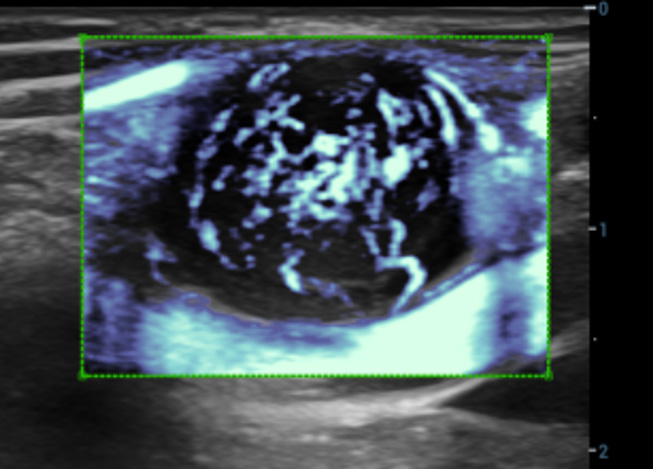

CEUS UWN+(Ultra-Wideband Non-linear)

CEUS tumore maligno al seno

Utilizzando sia i segnali fondamentali di seconda armonica che quelli non lineari, UWN+ consente un'elevata sensibilitĂ ai segnali delle microbolle e una perfusione di contrasto piĂč lunga con un MI piĂč basso, per contribuire alla valutazione dei tumori.